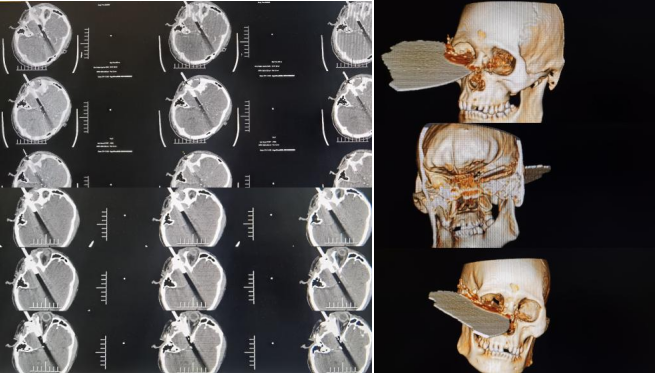

神经外科二病区付登礼教授团队联合多学科成功为一名颅内异物贯通伤患者完整取出飞入大脑深部并滞留10多小时的断裂切割锯1片,切割锯长达近30 cm,宽20 cm,其中嵌入异物大小约8x10cm,碎裂成数十块碎片,锈迹斑斑。术后患者神志清楚,语言功能、肢体运动功能良好,未见颅内感染征象。

患者入院时烦躁,意识模糊不对答,右侧头面部嵌入断裂切割锯,伤口从右颞经右眼眶底延伸至右鼻根,断裂切割锯一直嵌留于右侧头面部,伤口伴有活动性出血及脑脊液漏,双侧眼睑肿胀,睁眼困难。患者转入神经外科二病区后,科室高度重视,神经外科二病区付登礼教授团队立即组织抢救,初步诊断为开放性颅脑损伤中型、右额颞叶脑挫伤并脑内血肿、创伤性蛛网膜下腔出血、右额颞顶硬膜下血肿、左额颞硬膜下血肿、颅底骨折、颜面部开放性损伤。

时间就是生命,神经外科二病区立即为患者开放绿色通道,迅速指导家属办理入院手续,完成病史采集、体格检查,专人固定患者头部避免异物造成二次伤害,陪同患者完成相关CT扫描三维重建等相关影像学检查,明确患者病情,并组织眼科、耳鼻咽喉科、整形外科等相关科室对该患者进行联合会诊,完善术前准备。

颅内异物贯通伤通常受伤急、病情危重,容易感染、休克等,若处理不及时病死率高,该患者异物停留时间超过10小时,若不及时取出异物,患者生命将面临巨大风险。经多学科会诊共同评估手术风险并制定合理的手术计划后,患者于22:57分完善术前相关准备送入手术室实施“右侧额颞叶脑内血肿清除术、颅内异物取出术、开颅脑清创术、右侧眼眶及颜面部清创术”。

异物刺破患者硬脑膜进入颅内,脑出血、脑组织外漏,有脑脊液流出,大量破碎异物残留于皮下、颞肌及脑组织内。整个手术风险性高、难度大,神经外科二病区张崇进医生在付登礼主任指导下通过显微镜辅助彻底清除脑内血肿,同时清除异物周围挫伤脑组织、残留异物碎片及受污染脑组织,沿异物周围仔细探查。眼科医生沿异物刺入处皮肤向眶内进行探查,耳鼻咽喉科医生配合探查鼻腔,确认无大血管受损,张崇进医生再次确认颅内血管与异物无粘连,完整取出嵌入异物,异物取出后未见活动性出血。显微镜下沿异物入颅处再次仔细探查,未见活动性出血。